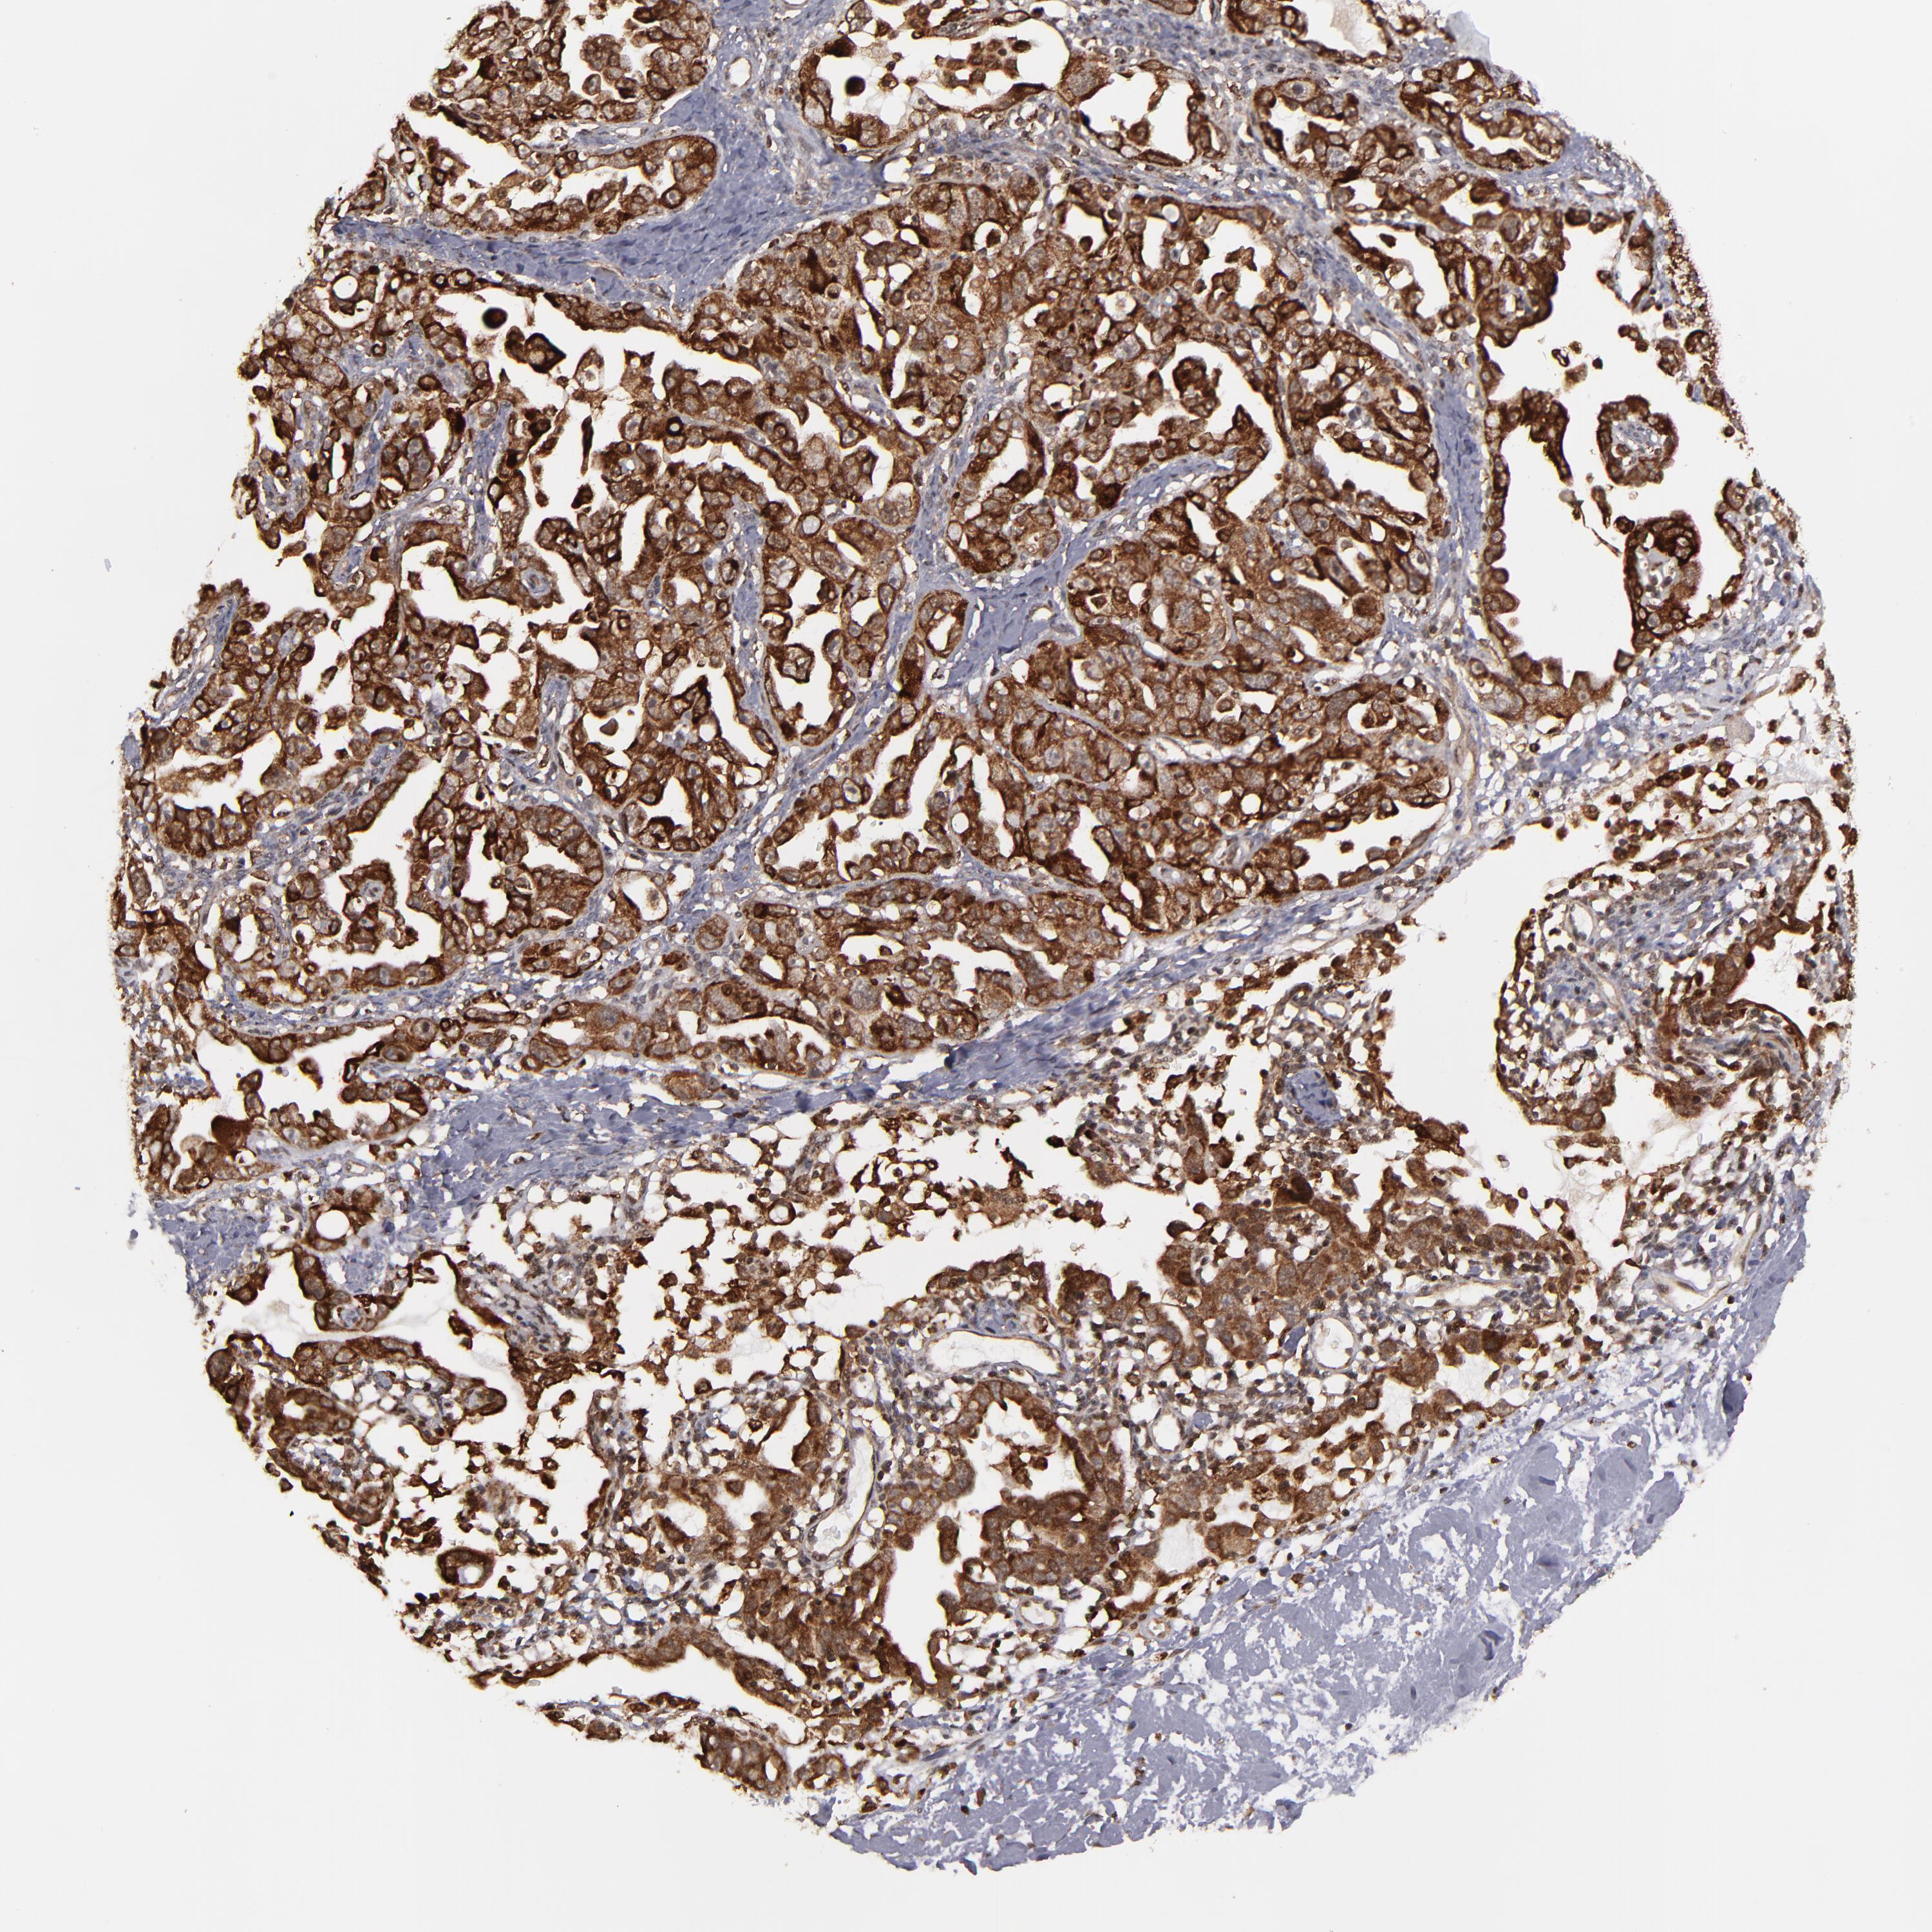

OVARIAN CANCER - Protein expressioni

A mouse-over function shows sample information and annotation data. Click on an image to view it in a full screen mode. Samples can be filtered based on level of antibody staining by selecting one or several of the following categories: high, medium, low and not detected. The assay and annotation is described here.

Note that samples used for immunohistochemistry by the Human Protein Atlas do not correspond to samples in the TCGA dataset.

Antibody stainingi

Antibody staining in the annotated cell types in the current human tissue is reported as not detected, low, medium, or high, based on conventional immunohistochemistry profiling in selected tissues. This score is based on the combination of the staining intensity and fraction of stained cells.

Each image is clickable and will lead to virtual microscopy that enables deeper exploration of all samples and also displays staining intensity scores, fraction scores and subcellular localization as well as patient and tissue information for each sample.

Antibody HPA003067

Cystadenocarcinoma, serous, NOS

Cystadenocarcinoma, mucinous, NOS

Carcinoma, endometroid